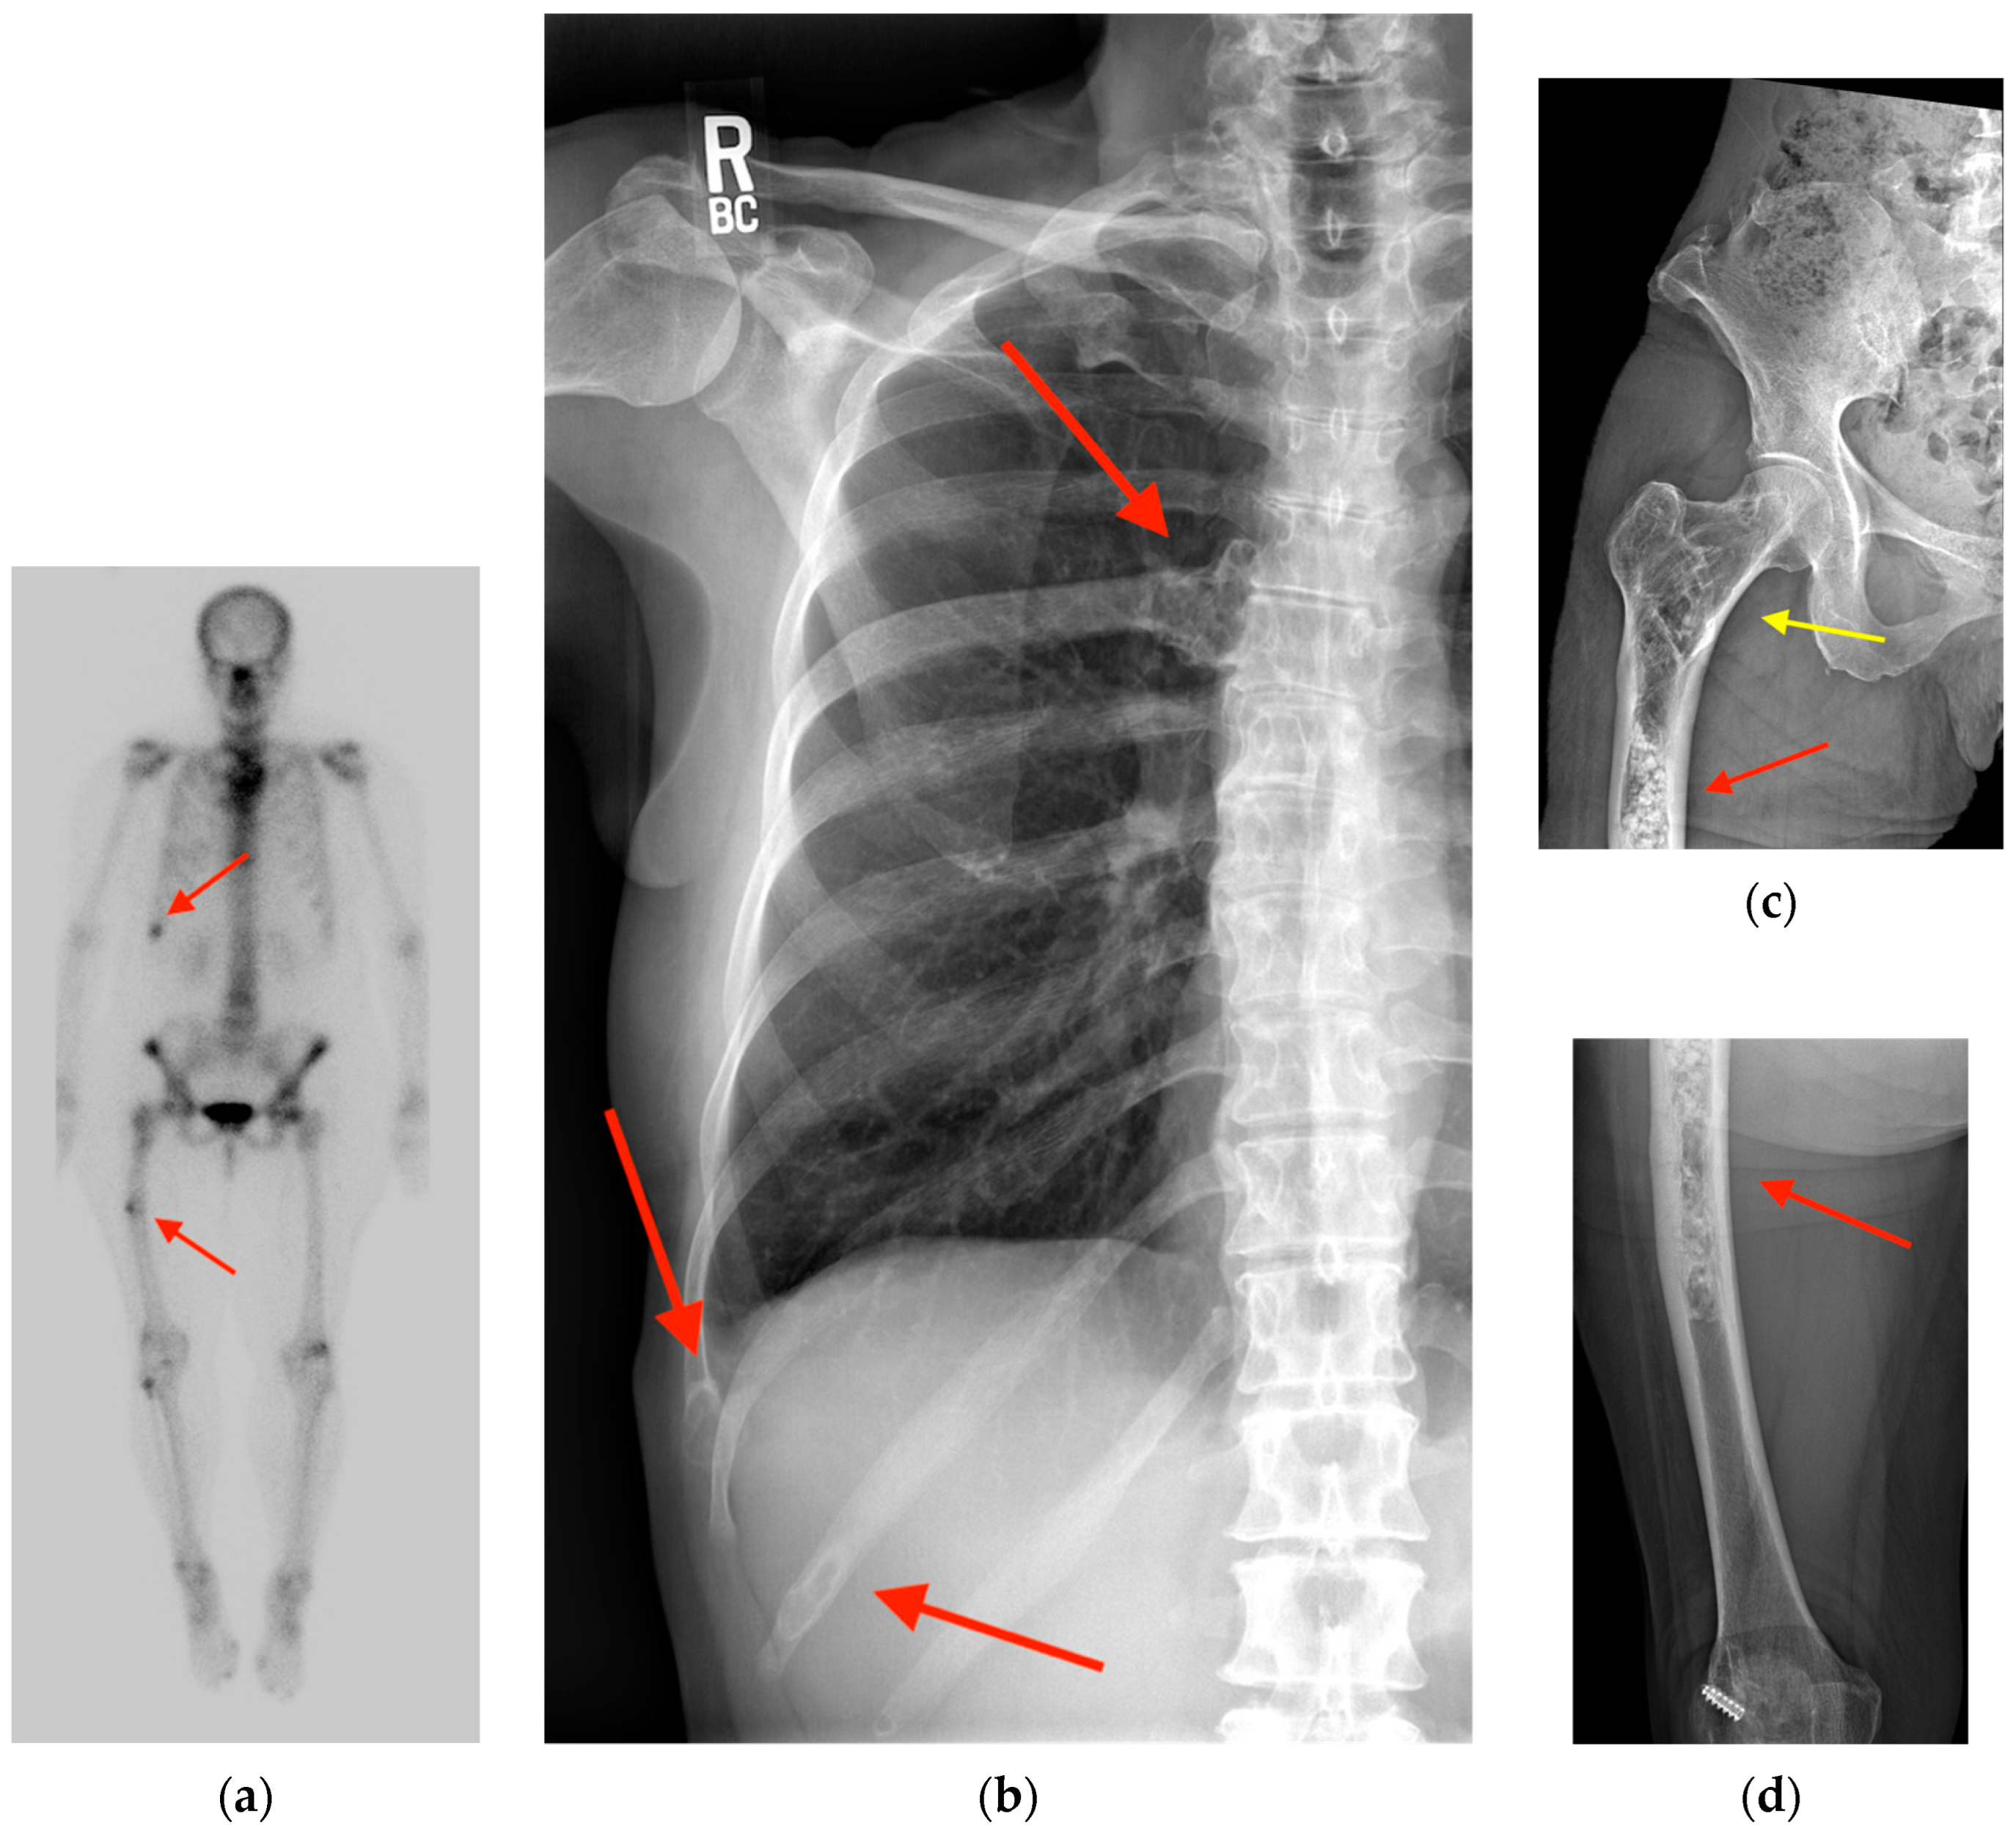

2.6. Paget’s Disease

- Ralston, S.H. Clinical practice. Paget’s disease of bone. N. Engl. J. Med. 2013, 368, 644–650. [Google Scholar] [CrossRef]

- Miller, S.W.; Castronovo, F.P., Jr.; Pendergrass, H.P.; Potsaid, M.S. Technetium 99m labeled diphosphonate bone scanning in Paget’s disease. Am. J. Roentgenol. Radium Ther. Nucl. Med. 1974, 121, 177–183. [Google Scholar] [CrossRef] [PubMed][Green Version]

- Park, E.T.; Kim, S.E. Radiography, Bone Scan, and F-18 FDG PET/CT Imaging Findings in a Patient with Paget’s Disease. Nucl. Med. Mol. Imaging 2010, 44, 87–89. [Google Scholar] [CrossRef] [PubMed][Green Version]

- Sasikumar, A.; Joy, A.; Nanabala, R.; Pillai, M.R.A.; Hari, T.A. 68Ga-PSMA PET/CT False-Positive Tracer Uptake in Paget Disease. Clin. Nucl. Med. 2016, 41, e454–e455. [Google Scholar] [CrossRef]